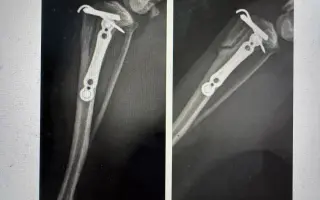

Po operaci druhé zadní nožičky se objevily komplikace – kontrolní RTG odhalilo frakturu kortexu (zlomenina namáhaného místa).

Po vyžádání RTG ze dne operace jsme zjistili, že fraktura se stala během zákroku, o čemž nám pan doktor neřekl. Díky prasklině musela být Willíčkovi navíc zavedena fixační destička s hřebem, nikoliv skrze prevenci, jak nám bylo nepravdivě sděleno.

Prasklina pracovala a bohužel praskla dál, viz snímek níže.